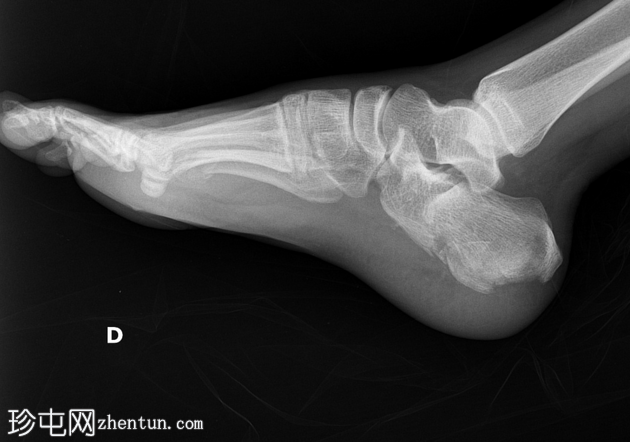

侧位

跟骨关节内骨折。

如果初始影像检查未能清晰显示关节内骨折延伸情况,则应评估Böhler角和Gissane角。本例中,Böhler角减小,Gissane角增大。这两个发现均证实了关节内跟骨骨折。